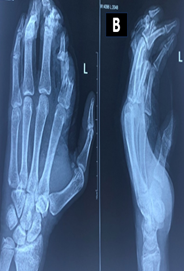

Burden, Treatment Patterns, and Functional Recovery of Hand Injuries in a Tertiary Hospital of Eastern India

Aparna Kanungo , Sanjay Kumar Giri , Sunil Kumar Rout , Ritesh Panda , Jagannatha Sahoo , Mantu Jain